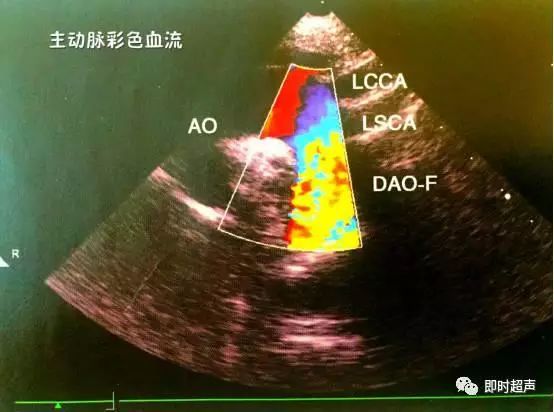

十、胸骨上主动脉弓长轴切面

主要观察:升主动脉、主动脉弓及降主动脉起始部的病变。

十一、胸骨上区降主动脉长轴切面

主要观察:降主动脉的病变。

十二、彩色多普勒血流成像